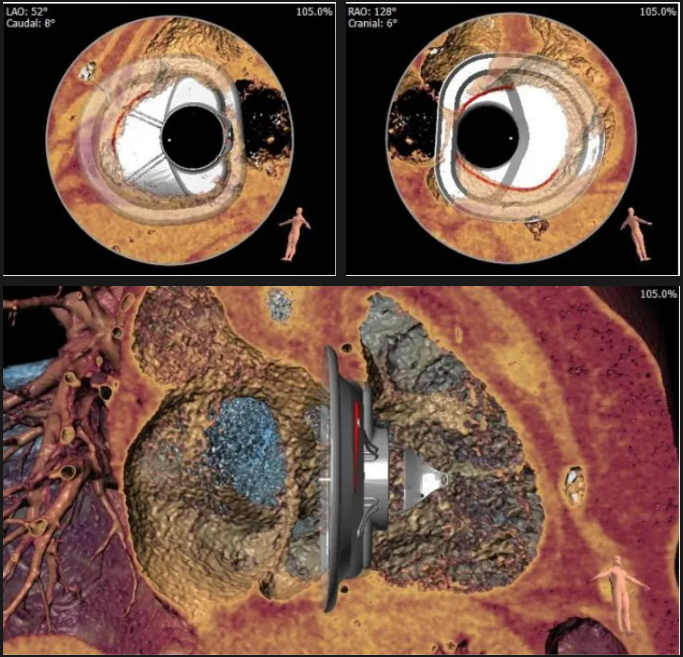

術(shù)前心臟CT評估

三尖瓣環(huán)平均周長徑54.3mm,最大直徑57mm

心房側(cè)周長平均徑(封堵高度)74.0mm

三尖瓣環(huán)切線位夾角 103°

夾持件位置確認(rèn)

室間隔位置確認(rèn)